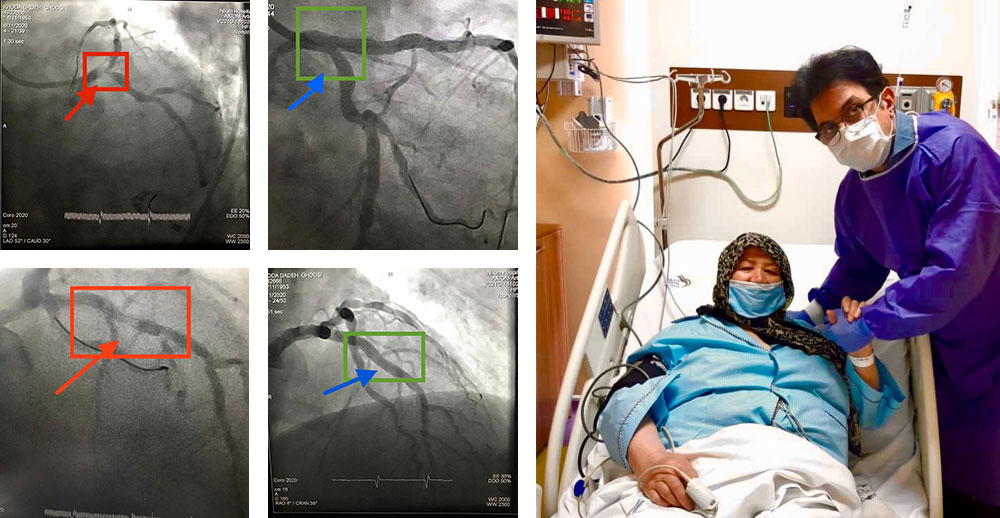

تنگی مدخل ورودی سیستم چپ عروق قلب

تا همین چند سال پیش راهی جز عمل جراحی اورژانس قلب باز نداشت. بیمار ما روز بعد از کارگذاری سه استنت در سیستم چپ به زندگی دوباره باز می گردد و قابل ترخیص است.

روش جدید درمان تنگی و گشادی متناوب شریان های قلب

با استنت هایی با قابلیت اتساع خود به خود، که منجر به شکل گرفتن و چسبیدن استنت در تمام طول به شدت نامنظم تنگی و گشادی رگ می شود. بیمار ۸۵ ساله ی ما، روز بعد از کارگذاری ۵ استنت در جریان آنژیوپلاستی از طریق شریان دست، قابل ترخیص است. بیمار فوق را به طور قطعی به جراحی قلب باز، ارجاع داده بودند.

انسداد کامل رگ

انسداد کامل رگ آخرین سنگر ناگشوده ی آنژیوپلاستی بود که با تکنیک های جدید، تا ۹۰٪ امکان بازگشودگی بدون جراحی قلب باز را دارد. بیمار اول انسداد کامل رگ راست و دومی انسداد کامل رگ چپ داشتند. هر دو بیمار از طریق هر دو شریان دست راست وچپ درمان و روز بعد بی هیچ عارضه یی مرخص شدند. ایمان بیاوریم به اعجاز روش های نوین آنژیوپلاستی!